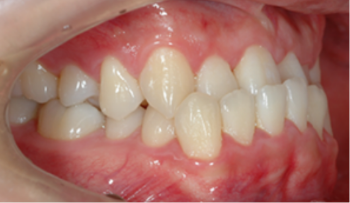

성장기 아동의 교정 치료

영구 치열의 교정 치료

수술을 위한 교정 치료

각 분과별 협진으로 치료하는 것이 효과적입니다.